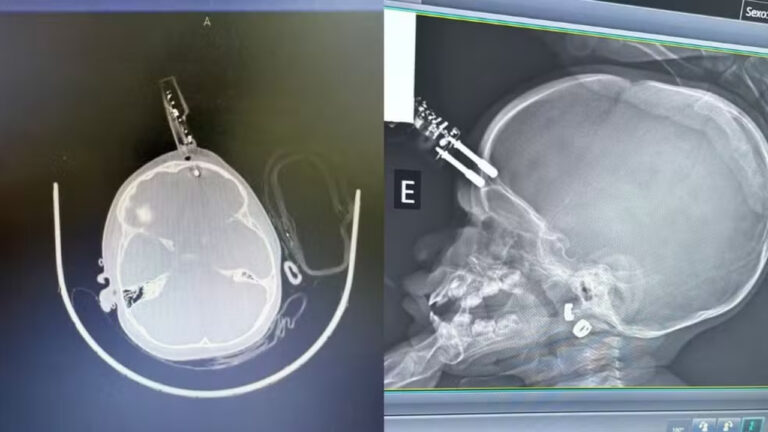

Uma menina de um ano foi submetida a uma cirurgia de urgência após sofrer um grave acidente doméstico em Divinópolis, no Centro-Oeste de Minas Gerais. A criança caiu da cama e teve um carregador de celular cravado na região frontal da cabeça, próxima ao olho. Segundo a equipe médica, ela permanece internada em observação e, até o momento, não apresenta sinais de sequelas neurológicas.

De acordo com o neurocirurgião Bruno Castro, responsável pelo atendimento, a principal hipótese é que a menina estava com o carregador na mão no momento da queda, o que fez com que o objeto atingisse a cabeça de forma perfurante.

Após o acidente, a criança foi levada imediatamente para atendimento hospitalar e encaminhada ao bloco cirúrgico. No local, passou por procedimentos de limpeza da área afetada, retirada do objeto, lavagem, fechamento e reconstrução da região atingida.

A intervenção foi considerada essencial para evitar infecções e possíveis complicações neurológicas mais graves.

Segundo o médico, a paciente está recebendo antibiótico profilático, conforme protocolo adotado em casos de lesões perfurantes no crânio. Até o momento, não há indícios de comprometimento neurológico.